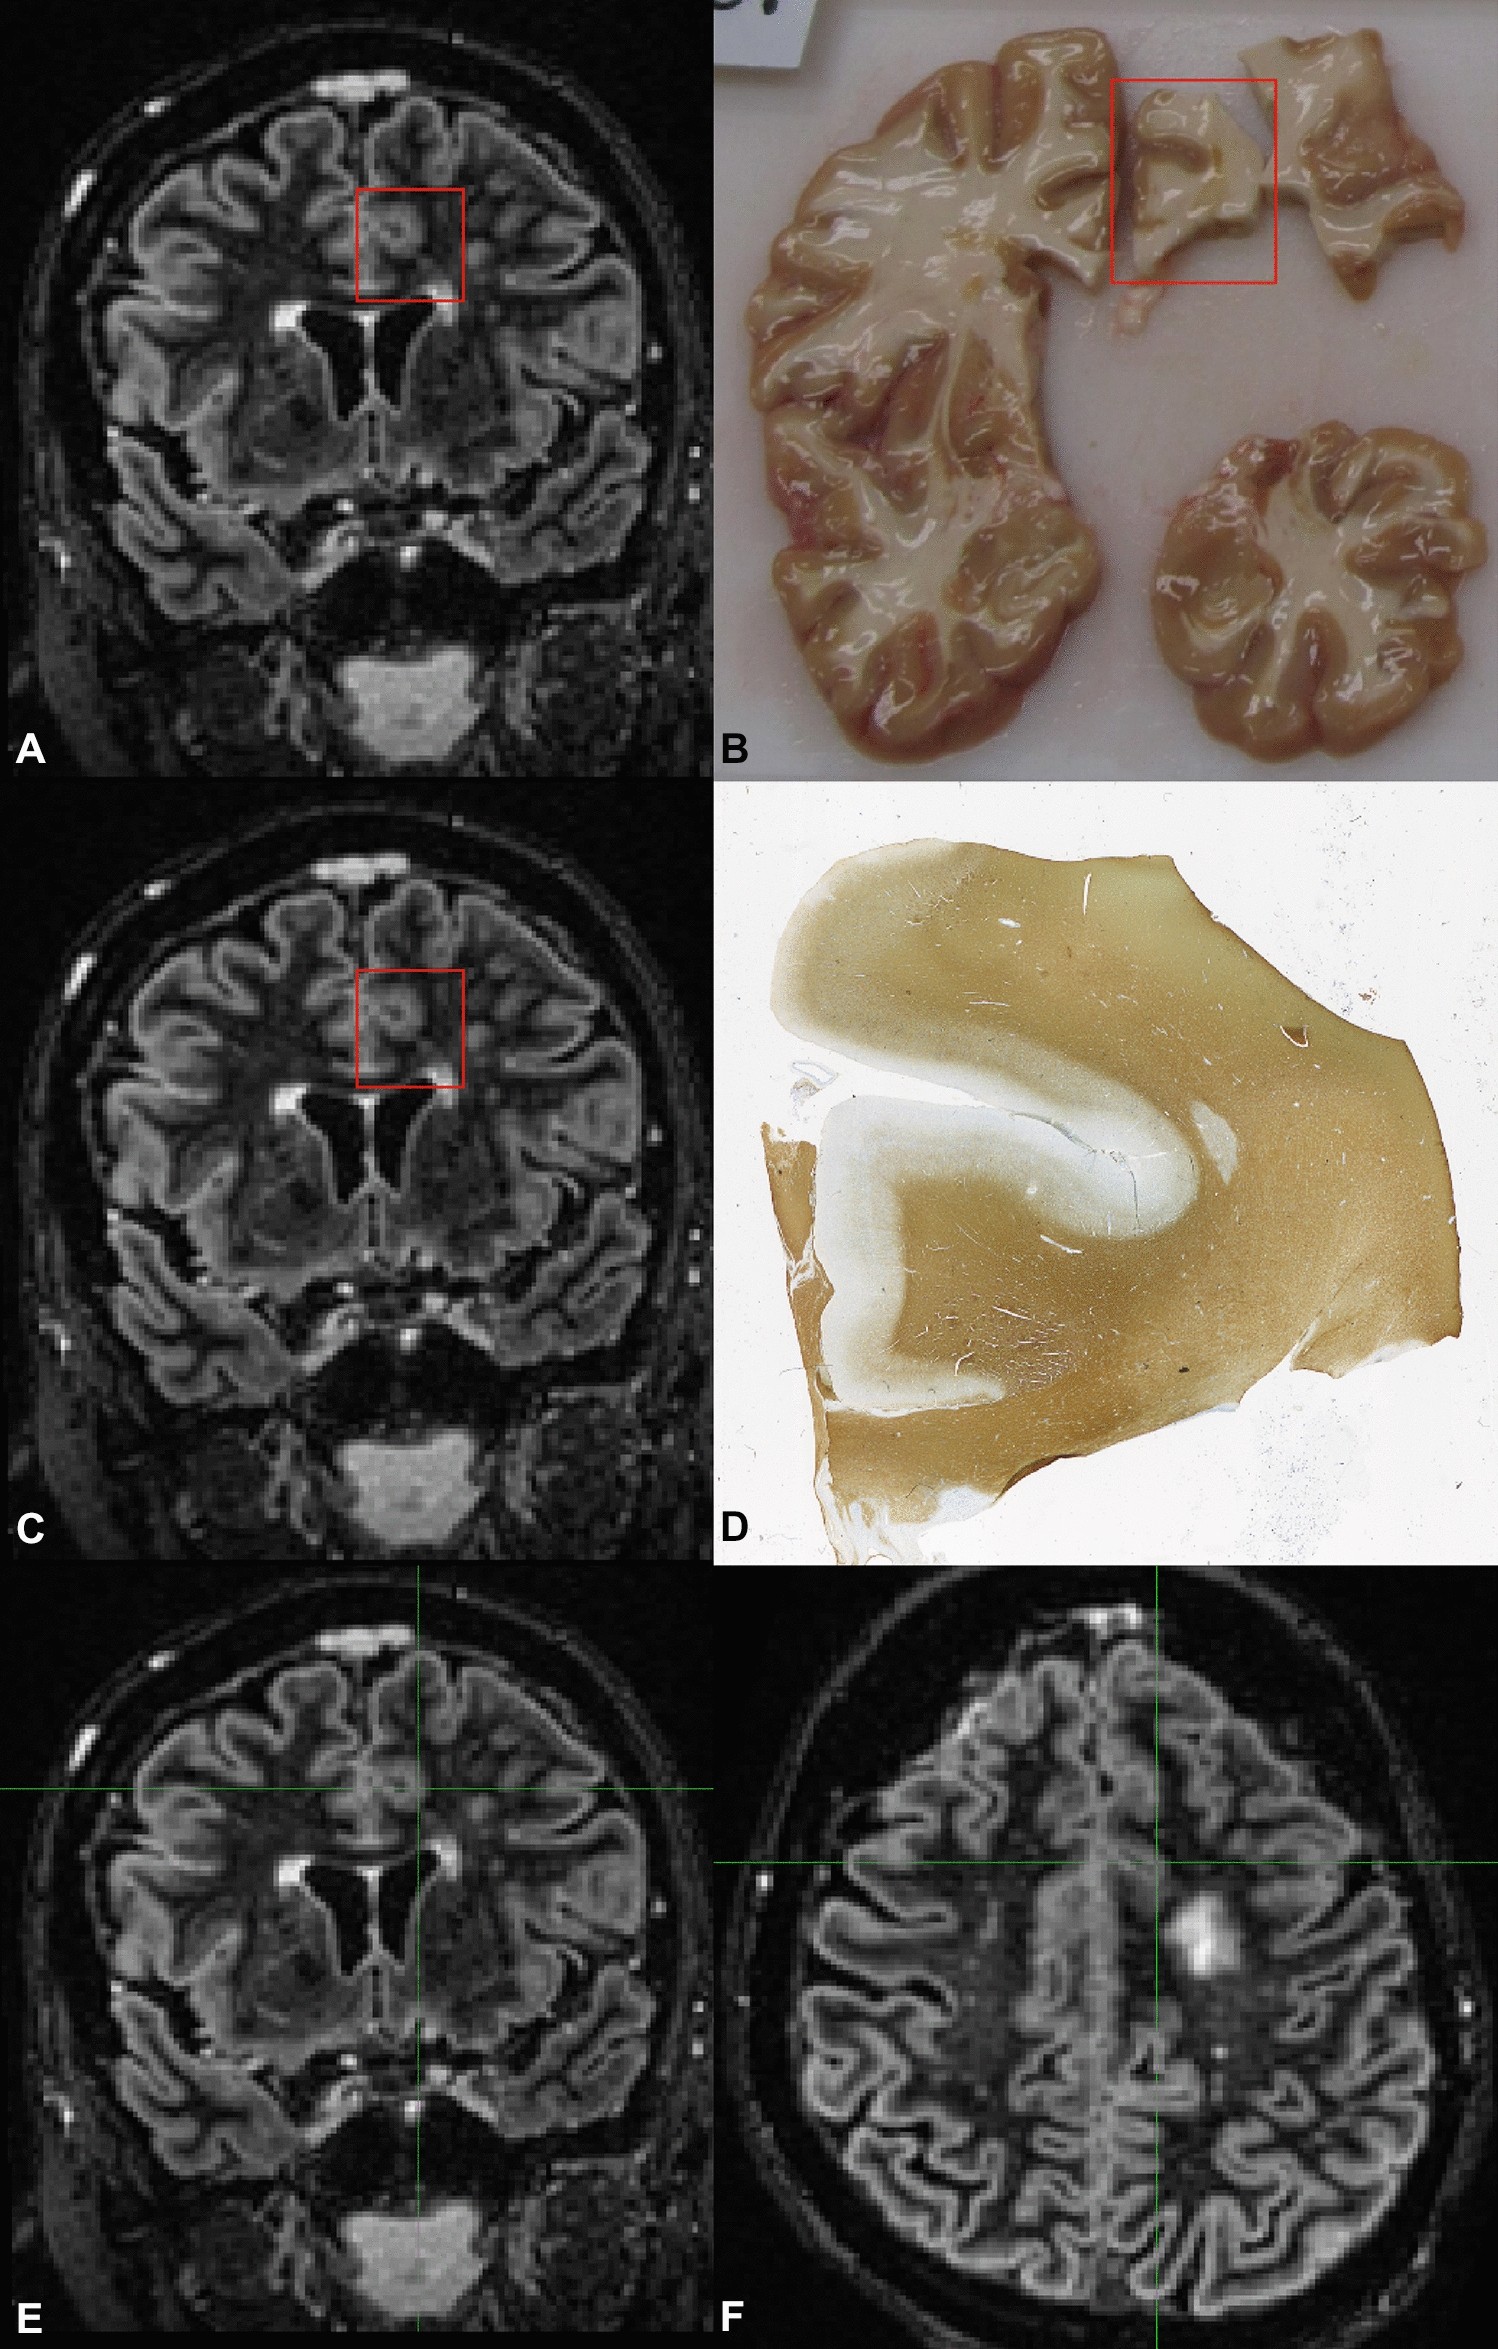

Figure 3

Overview of the histopathological tissue sample to MRI matching procedure. (A) The coronal double inversion recovery (DIR) MRI is matched to (B) a photograph of the tissue sample. Then, the coronal DIR MRI (C) is matched to the histopathological sample (D) coming from the tissue sample. Next, the cross-hair is used to translate the histopathological tissue sample location from the coronal DIR (E) to the axial DIR (F); (generated using Adobe Illustrator—Adobe Inc., 2019. Adobe Illustrator,